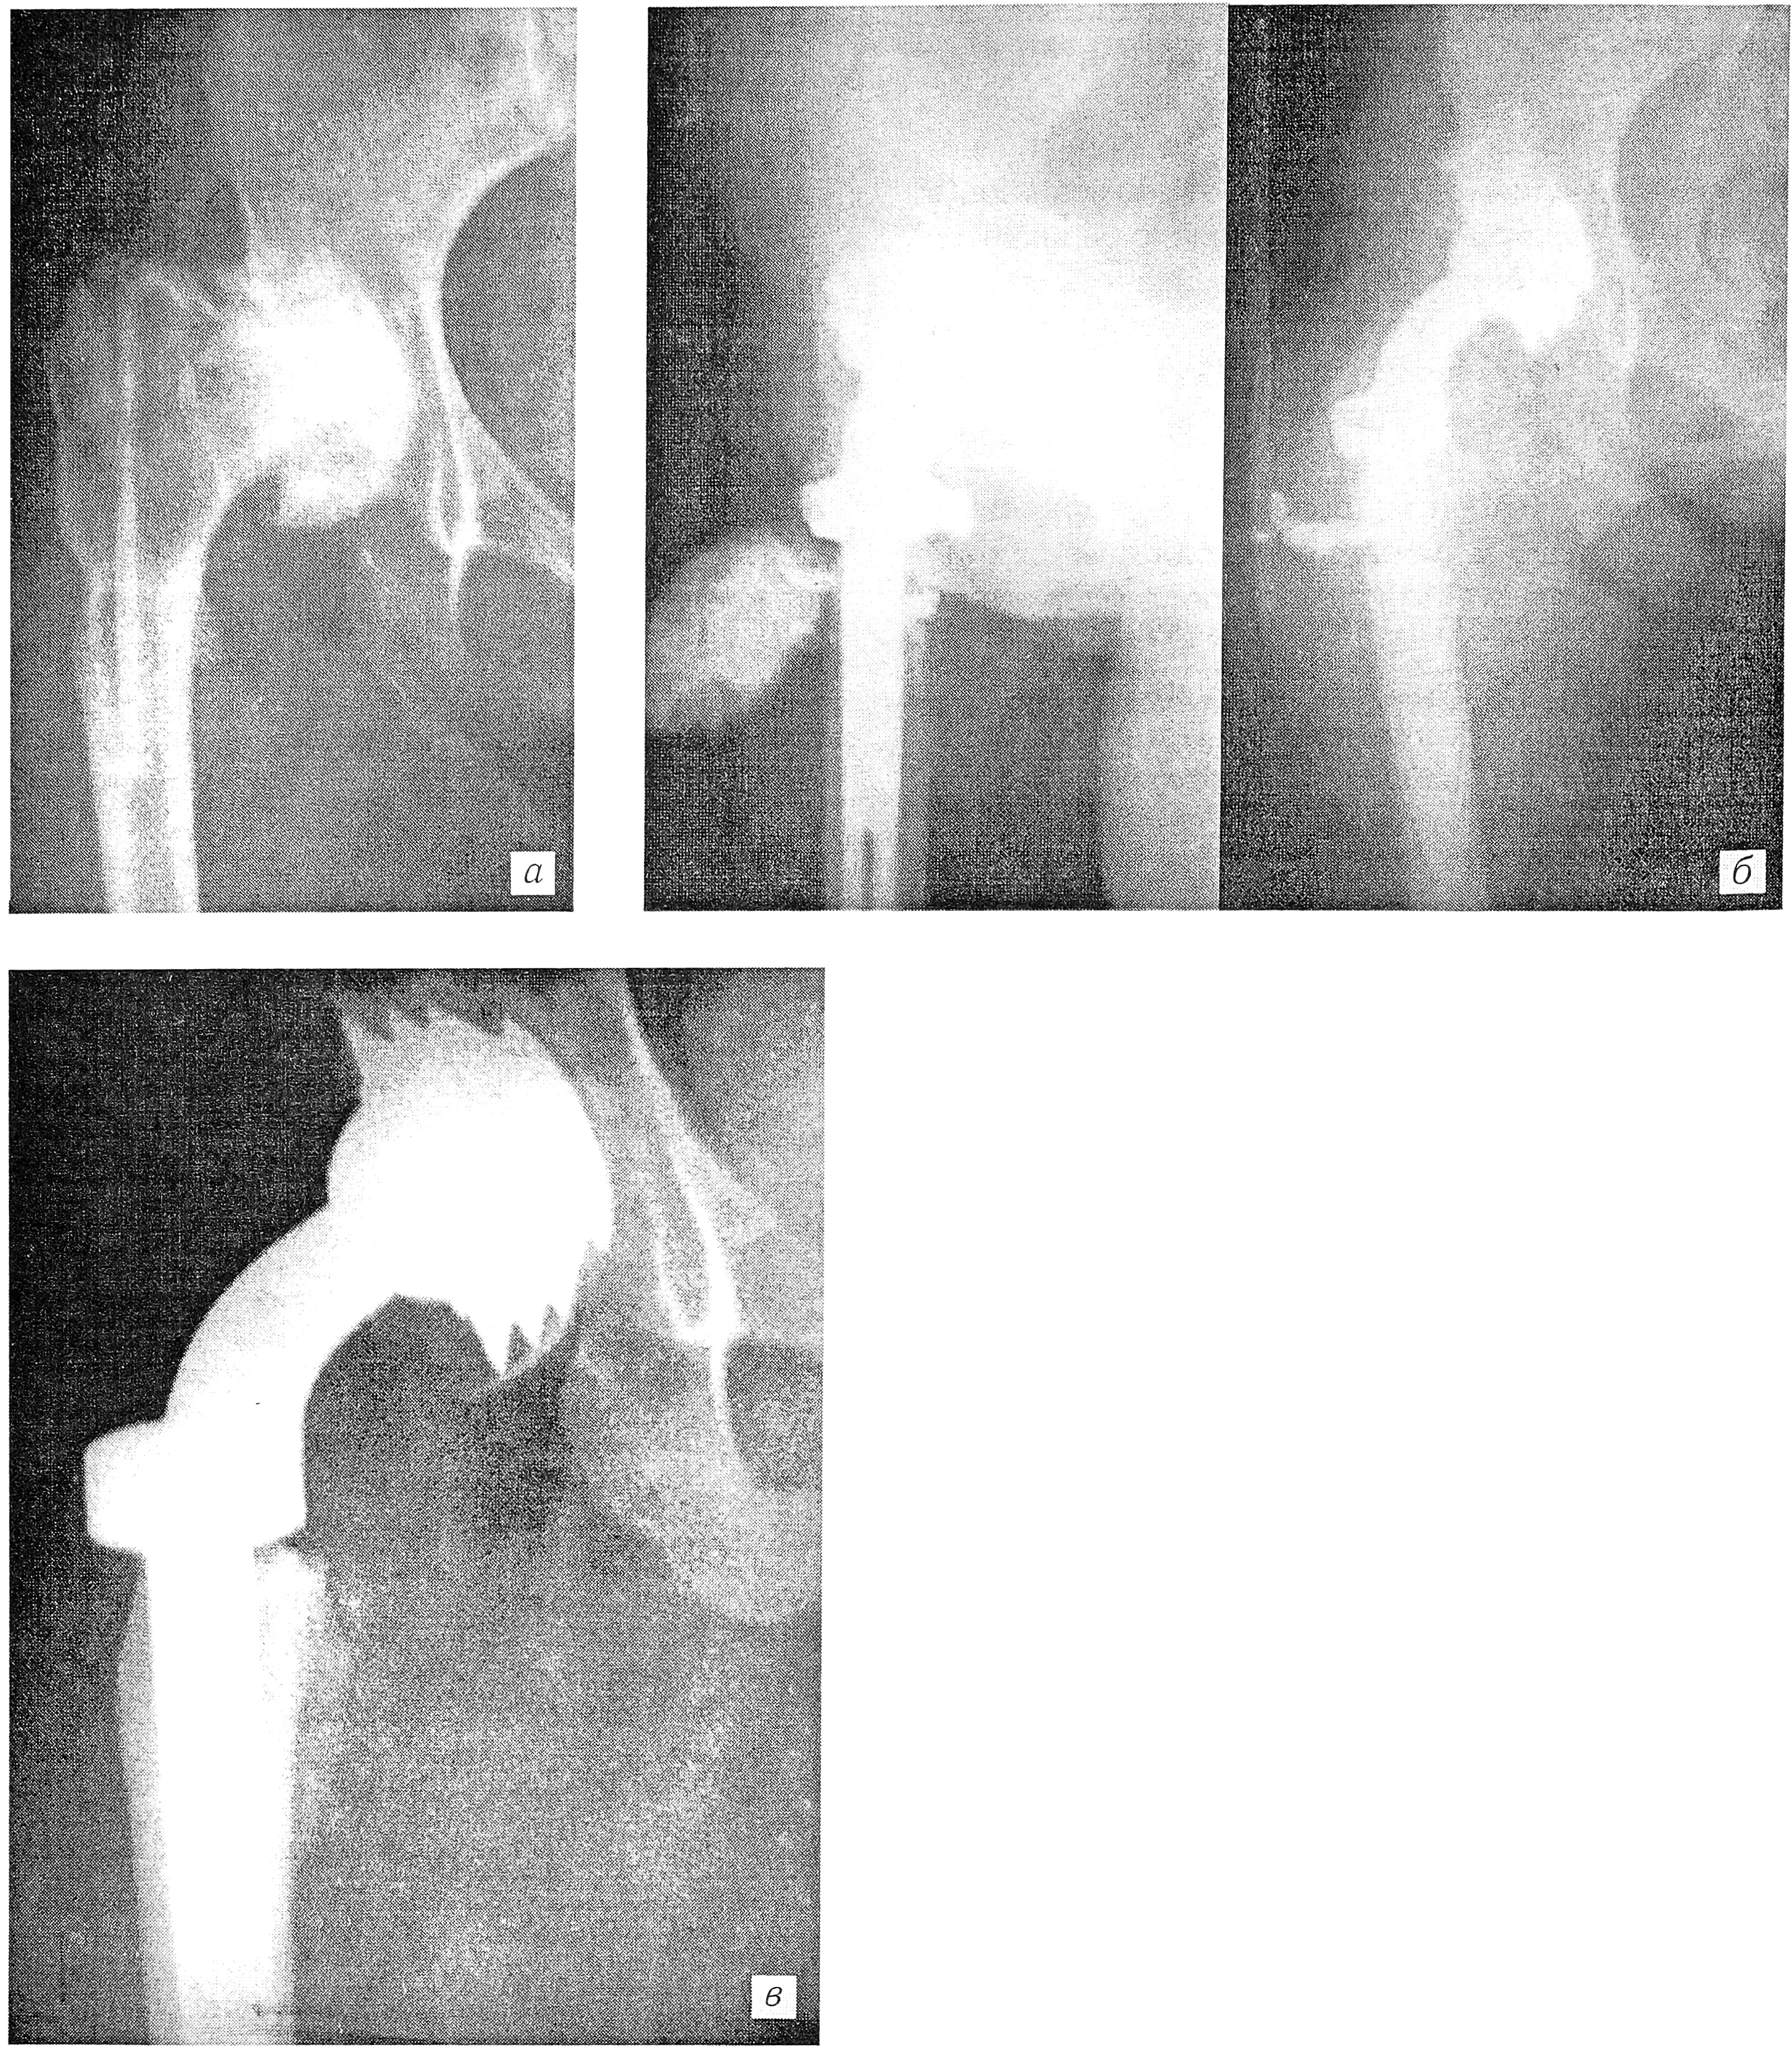

Больной Р., 1957 г. рождения. С 2-летнего возраста страдал туберкулезным кокситом. Получал санаторное лечение и противотуберкулезную химиотерапию. Туберкулезный процесс был ликвидирован, но развился деформирующий артроз правого тазобедренного сустава. 20.06.76 больной оперирован (г. Кишинев): произведена артропластика аллоколпачком (см. рисунок, а). Боли и ограничение подвижности в тазобедренном суставе сохранялись.

Рис. 1. Рентгенограммы правого тазобедренного сустава больного Р.

а — после артропластики; б — после резекции проксимального метаэпифиза с эндопротезированием (произведена фистулография через функционирующий свищ); в — через 5 лет после эндопротезирования.

24.01.77 предпринята резекция головки и шейки бедренной кости с эндопротезированием по К.М. Сивашу. Через 2 нед после операции выделилась небольшая гематома, но рана зажила первичным натяжением. Сохранялись умеренно выраженные боли в оперированном суставе, повышенная СОЭ, отмечались подъемы температуры в пределах 37,1—37,3°С. В октябре 1977 г. открылся свищ (см. рисунок, б). При посеве отделяемого из свища выделен гемолитический стафилококк. Произведена катетеризация бедренной артерии. Внутриартериально вводились антибиотики направленного действия, аммарген капельно, а в свищ — препараты папаина. Через 3 нед свищ закрылся. В течение 3 мес больной получал линкомицин в капсулах. Через 5 лет здоров (см. рисунок, в). Свища нет. Хорошо пользуется оперированной конечностью.